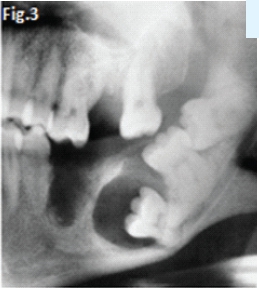

Fig 1 & 2: the large lesion of left mandible shows a honeycomb-like distribution of calcifications. The borders are corticated. The tumour has displaced the mandibular molar tooth. A histological diagnosis of calcifying epithelial odontogenic tumour (Pindborg Tumour) was made. Fig.3 shows a Pindborg tumour distal to left second premolar associated with displacement of the first molar tooth. Fig.4 shows a similar tumour with mixed lucency-opacity between right premolar and molar teeth. Figs 5 & 6 show coronal and axial CT views of a large Pindborg tumour affecting the right maxilla. Note the marked expansion and cortical destruction. Calcifying epithelial odontogenic tumour is a rare benign neoplasm, accounting for less than 1% of all odontogenic tumours. The average age at diagnosis is 40 years; however, the tumour can occur at any age. It occurs equally in males and females. Approximately two thirds of cases are reported to occur in the mandible. Most cases occur in the premolar-molar area and are commonly associated with an unerupted tooth. The tumour is a painless, slowly enlarging mass. Histologically the tumour has a very characteristic appearance. Sheets of polyhedral cells with well-defined eosinophilic cytoplasm and hyperchromatic nuclei are featured. Amyloid and ringlike calcification may also be present. The tumour may be irregular or, in some cases, the cystic lesions may be well defined and corticated, whereas others appear ill defined. Small unilocular lesions may have a completely radiolucent centre (Fig.3). Others may have variable amounts of small flecks of calcifications scattered throughout. Larger lesions have a multilocular or honeycomb appearance. The tumour can displace and often prevent the eruption of teeth. Radiologically the tumour may be very similar to the calcifying odontogenic cyst, adenomatoid odontogenic tumour and ameloblastic fibro-odontoma.